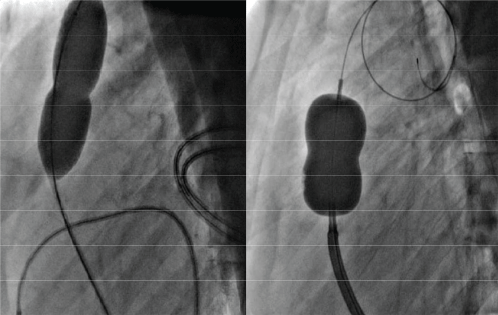

Figure 2: Serial Pulmonary valve balloon dilatation with 18 mm × 4 cm Tyshak balloon and 23 mm Inoue balloon catheter.